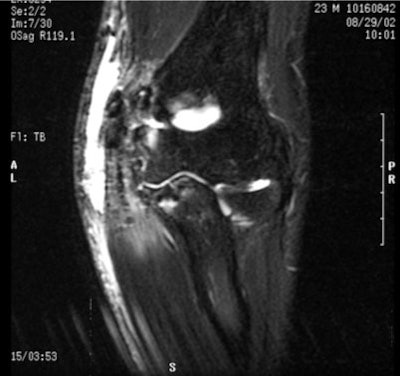

Ulnar Collateral Ligament Tear of the Elbow

History: A 23-year-old male pitcher delivered a pitch and felt a very distinguishable "pop" in his elbow. He could not deliver another pitch and was immediately taken out of the game. Clinical examination showed obvious swelling of the medial aspect of the elbow with lack of flexion and extension. Tenderness was present along the medial elbow, but specifically just distal and posterior to the medial epicondyle. Valgus stress testing in 30° of flexion was very painful. MRI confirmed the diagnosis of complete tear of the ulnar collateral ligament. Significance: Although this can happen in any thrower, the injury occurs most often in pitchers. Interestingly, these acute injuries occur in game situations and not in practice, undoubtedly because of the velocity of the pitch. The throwing motion inherently places a valgus stress on the ulnar collateral ligament. Increasing the velocity increases the valgus stress, and is most likely why it occurs in games. Treatment: Acute ruptures of the ulnar collateral ligament are treated with surgical reconstruction, usually utilizing the palmaris longus, although other tendons can be used. Primary repairs have been tried, and some have been successful, but the so-called "Tommy John" surgery (a procedure wherein a tendon is taken from the non-pitching arm to replace the torn ligament) is the gold standard for this injury. Return to competition usually takes 12-16 months. Image and case study courtesy of the San Francisco Giants. |